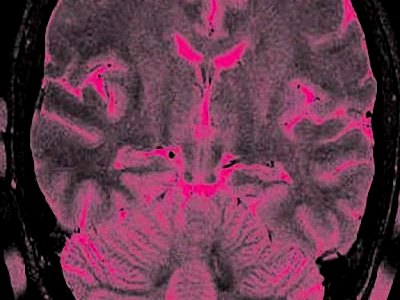

Các chuyên gia Pháp vừa hủy thành công các u di căn trong não bằng tia lade. Phương pháp này sử dụng công nghệ hình ảnh cộng hưởng từ hạt nhân mà không cần mở hộp sọ.

Khi đã định vị được khối u và đã luồn dây quang vào trong hộp sọ, lade bắt đầu được kích hoạt và đốt nóng khối di căn trong vòng một đến hai phút rồi hủy khối di căn. Một hệ thống tin học cho phép điều chỉnh năng lượng do lade giải phóng ra, hơi nóng được kiểm soát 3 giây một lần để không vượt quá 90 độ. Các bản đồ nhiệt cho phép nhận ra những vùng đã bị hủy.